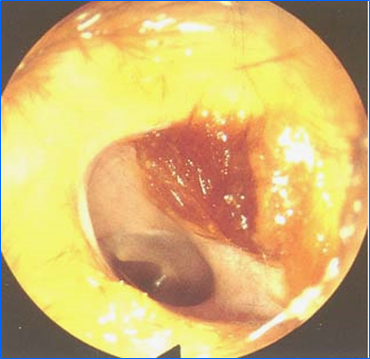

5、鼓膜检查的内容

注意观察鼓膜的形状、位置、颜色和标志:

• 鼓膜形状:正常鼓膜呈椭圆形浅漏斗状。

• 鼓膜位置:向前外下倾斜,小儿倾斜尤为明显。

• 鼓膜颜色:珍珠样银灰色,半透明,有光泽。

• 鼓膜的标志:鼓脐—位于锤骨柄的末端处,鼓膜紧张部的中央。光锥—自锥骨柄末端向前下达鼓膜边缘的一个三角形反光区。前、后皱壁 —自锤骨短突到鼓膜前、后边缘的皱壁。

• 松弛部:鼓膜前后皱襞以上外听道下壁以下的鼓膜。

• 紧张部:鼓膜前后皱襞以下外听道下壁以上的鼓膜。

正常鼓膜像